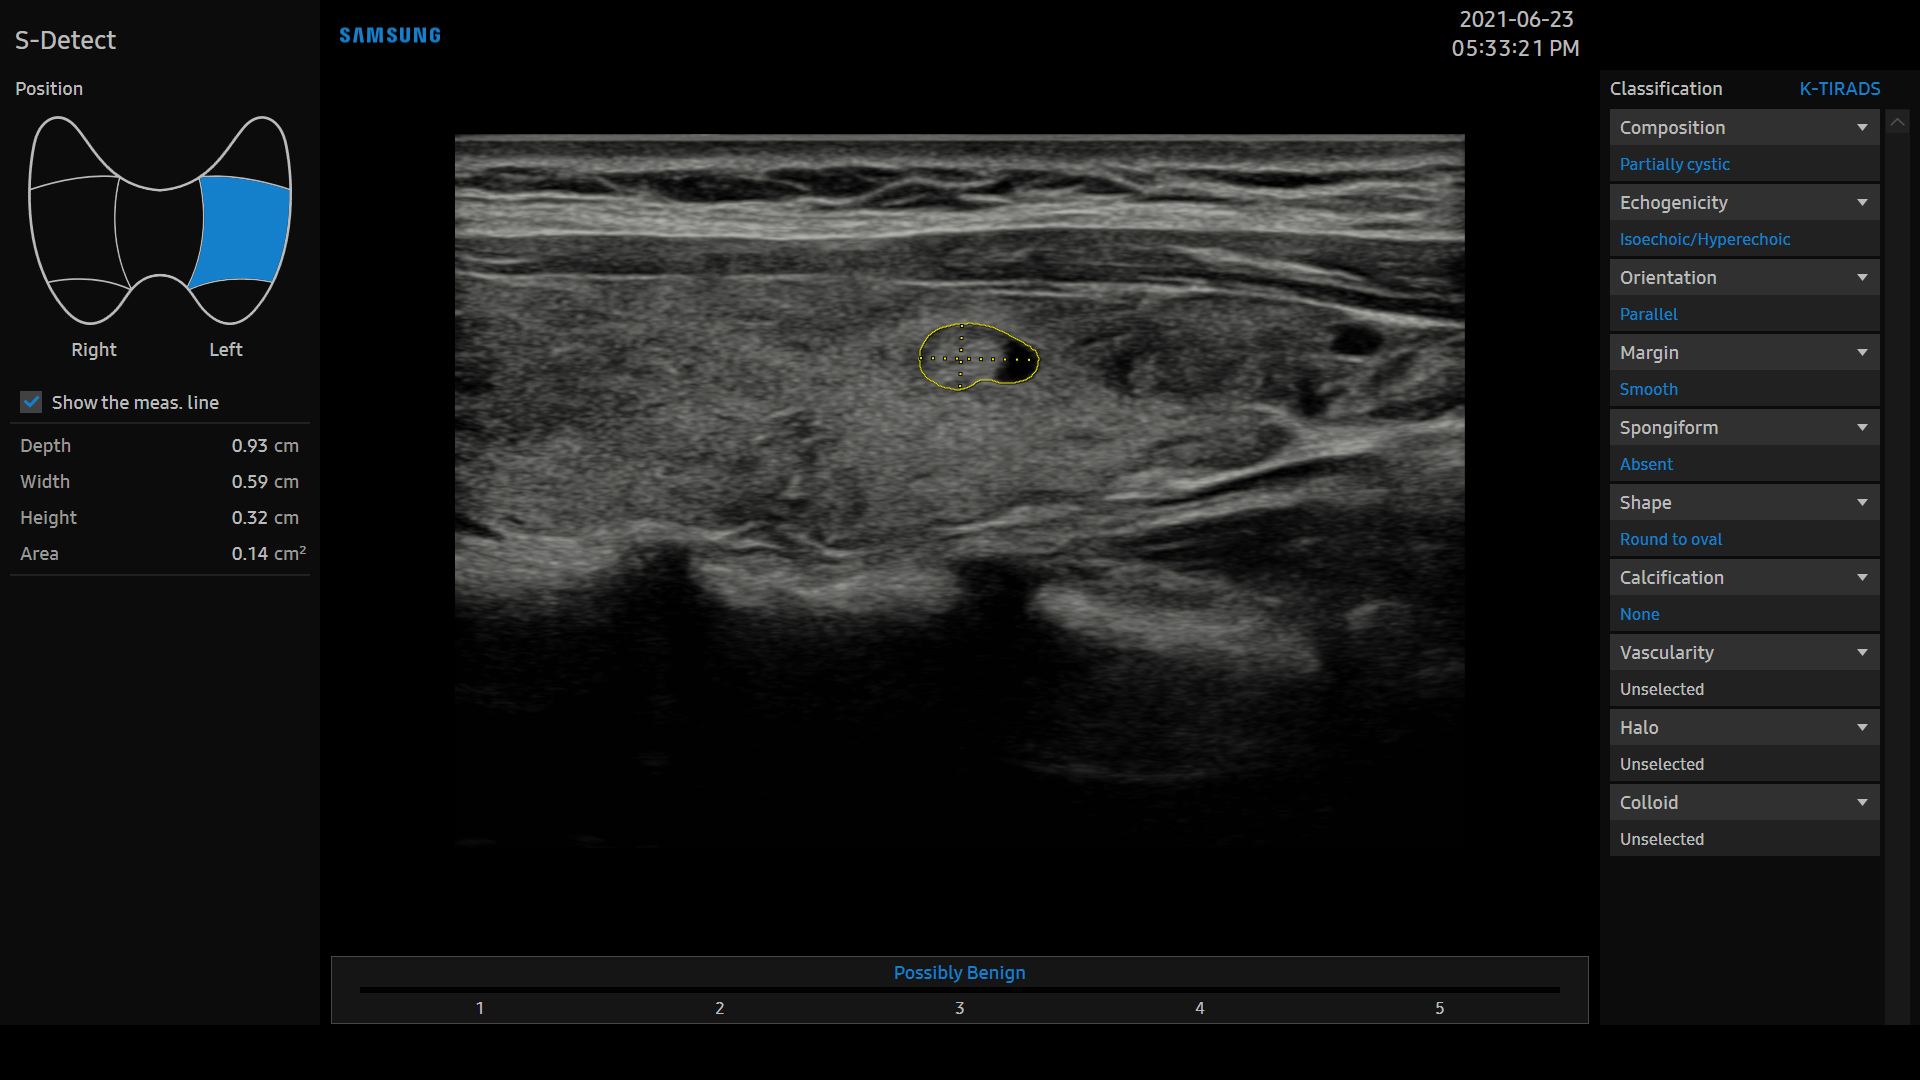

S-Detect™ for Thyroid utilise la technologie avancée qui se base sur les critères ATA, BTA, EU-TIRADS et K-TIRADS* pour la détection et la classification semi-automatiques des lésions thyroïdiennes suspectes. Cette technologie permet d'établir des diagnostics avec aisance, tout en fournissant des résultats cohérents et une fonction de génération automatique de compte rendus.

* ATA: American Thyroid Association - BTA: British Thyroid Association - EU-TIRADS: European Thyroid Imaging, Reporting and Data System- K-TIRADS: Korean Thyroid Imaging, Reporting and Data System